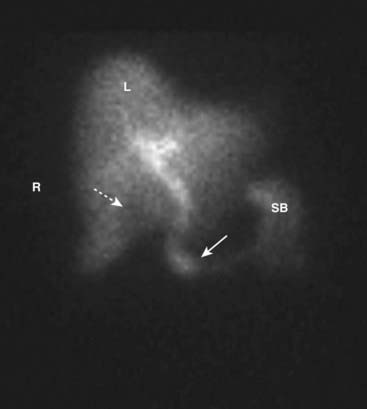

image In a normal HIDA scan, the bile ducts contain radiotracer within 10 minutes and there is radiotracer in the duodenum by 60 minutes, indicating patency of the common bile duct. Filling of the normal gallbladder occurs within 30 to 60 minutes, which confirms the patency of the cystic duct. Delayed images in several hours are usually obtained to reduce false positive results (Fig. 22).

image

Figure 22 Normal HIDA scan.

In a normal HIDA scan, the bile ducts (solid white arrow) contain radiotracer within 10 minutes, and there is radiotracer in the duodenum and small bowel (SB) by 60 minutes, indicating patency of the common bile duct. Filling of the normal gallbladder (dotted white arrow) occurs within 30 to 60 minutes, which confirms the patency of the cystic duct. Delayed images in several hours may be obtained to reduce false positive results. (R, Patient’s right side; L, liver.)

image Except in rare exceptions, visualization of the gallbladder excludes acute calculous cholecystitis.